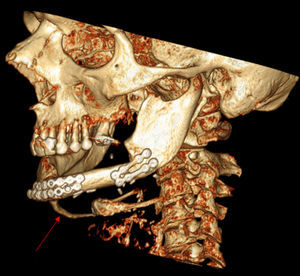

A bone scan was performed, showing localized technetium uptake in the mandible. An axial minimum intensity projection CT scan of the neck (MIP) (Fig. 1) and a 3D reconstruction (Fig. 2) were subsequently performed, showing an abnormal calcification linear stretching from the lower border of the mandible to the hyoid, following the anterior digastric muscle.